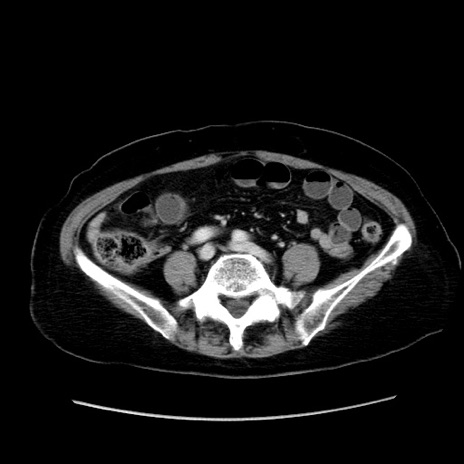

冠状断像

症例19(横断像)

【症例】80歳代女性

【主訴】下腹部痛

【現病歴】約8時間前より下腹部痛の出現あり、救急外来受診。

【既往歴】両側付属器切除

【身体所見】意識清明、下腹部正中に手術痕あり、その部位に一致して圧痛と反跳痛あり。腸蠕動音は亢進。

【データ】WBC 9300、CRP 0.15